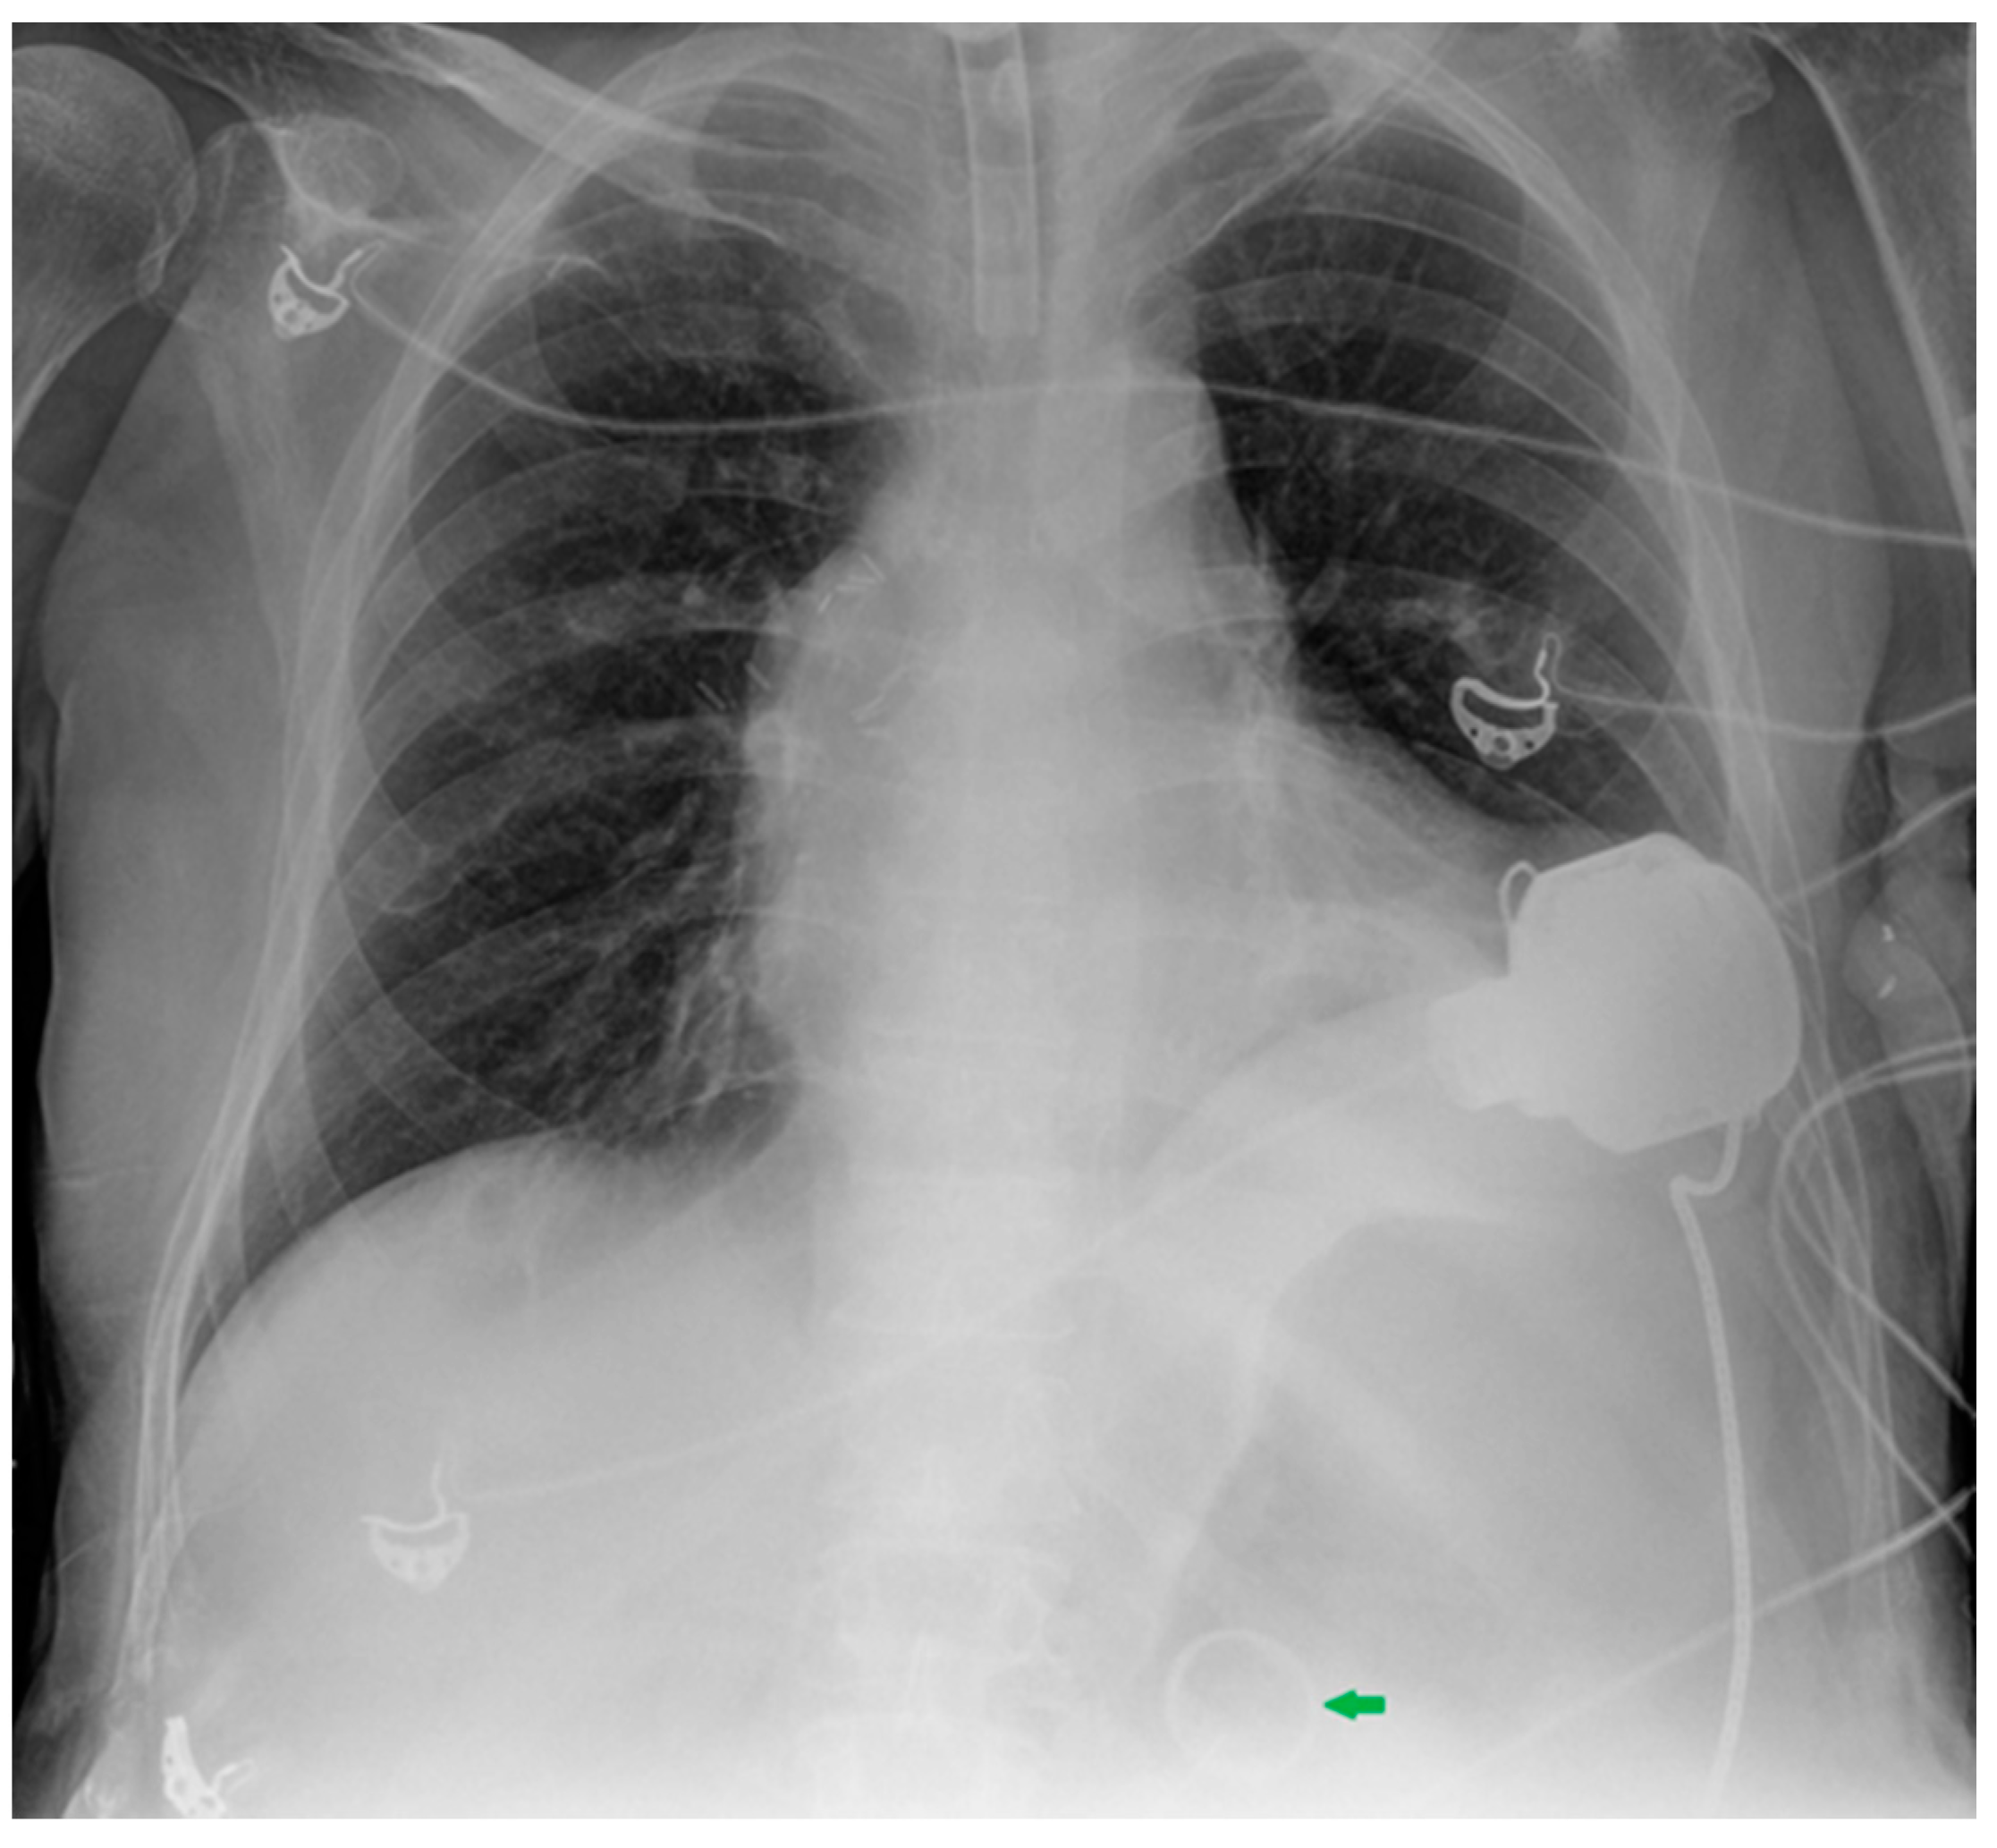

Figure 30.

Images of a right pleural effusion before (a) and after (b) drainage through an inferior-posterior chest tube. Right enlargement of the upper mediastinum is also present.